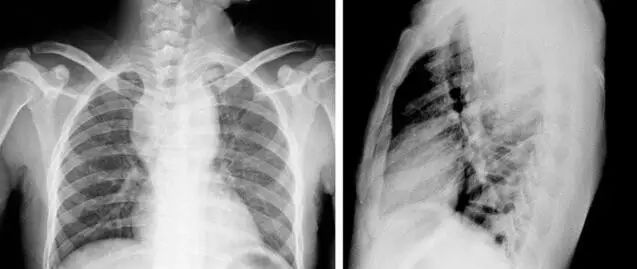

虽然经过对症药物治疗,萧萧体内的寄生虫已经被杀灭,但医生表示,肺吸虫已经对萧萧的身体造成了永久性的伤害。“通过CT检查,在萧萧的肺部可见到明显的空洞,这正是肺吸虫游走肺内留下的痕迹。”

肺部空洞 资料图片